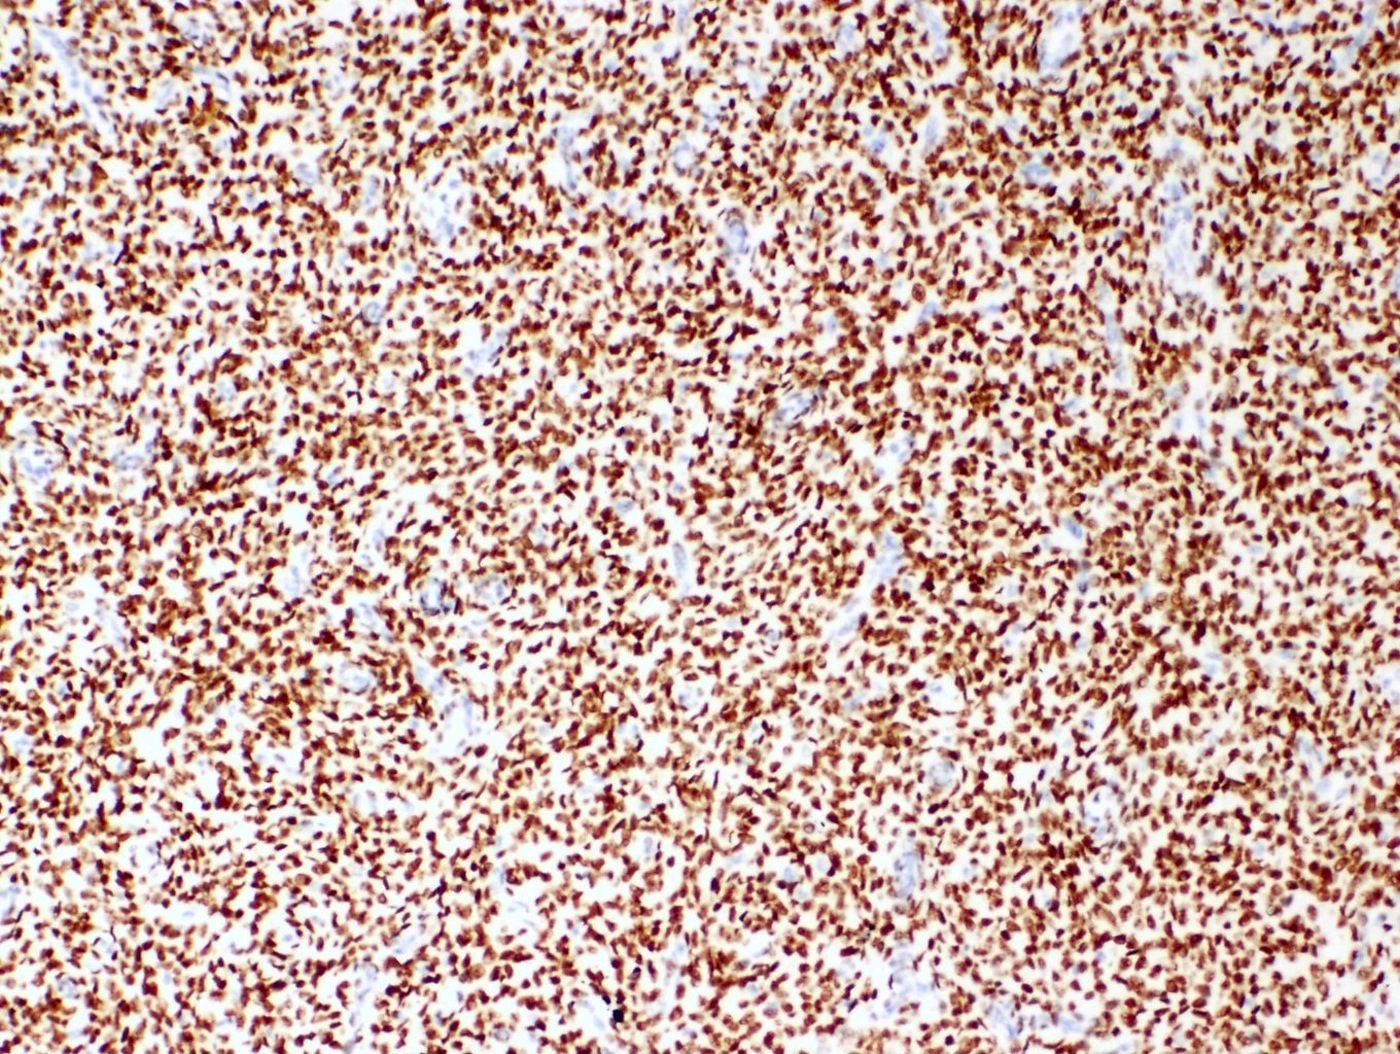

Positive stains

- CD10: sensitivity 91%, specificity 45% (Int J Gynecol Pathol 2018;37:372)

- IFITM1: sensitivity 83%, specificity 70% (Int J Gynecol Pathol 2018;37:372)

- WT1, ER (40 - 100%), PR (69 - 100%)

- Keratins: AE1 / AE3, CAM5.2, MNF 116, CK8 / 18

- Smooth muscle markers (SMA, desmin, caldesmon) often positive in areas of smooth muscle differentiation

- Sex cord markers (inhibin, calretinin, CD99, MelanA, WT1) may be positive in areas of sex cord differentiation

- Beta catenin: nuclear staining without associated mutation (Mod Pathol 2008;21:756)